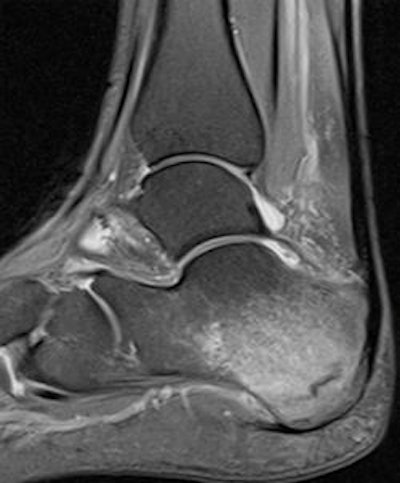

27-year-old female marathon runner. Sagittal STIR MRI shows calcaneal stress fracture paralleling posterior cortex with surrounding marrow edema. Image courtesy of Dr. Justin Lee, Chelsea and Westminster Hospital, London.27-year-old female marathon runner. Sagittal STIR MRI shows calcaneal stress fracture paralleling posterior cortex with surrounding marrow edema. Image courtesy of Dr. Justin Lee, Chelsea and Westminster Hospital, London.